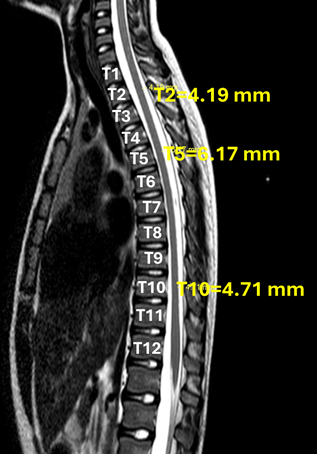

In a previous study MRI, the distance between the dura mater and the spinal cord in a female patient was evaluated in the thoracic segments of T2, T5 and T10 (Figure 2).

Figure 2 Distance between dura mater and spinal cord with MRI.

Measurement of the space between the dura mater and the thoracic spinal cord in MRI scans in one woman out of 50 patients showed values of 4.19 mm in T2, 6.17 mm in T5 and 4.71 mm in T10, as shown in Figure 2. This space allows the entry of a cutting needle that has a terminal hole at its tip, whereas the orifice of the pencil needle starts at 1.25mm and corresponds to another 0.75mm until its end, thus requiring the needle to be inserted more than 2mm, within the subarachnoid space for CSF return.3 In the case of the CSE technique, the set with a needle inside the needle was used, with a hole at the tip of the epidural needle (Huber) and the spinal anesthesia needle was the cutting tip, with no paresthesia occurring during its insertion. The insertion of the epidural catheter went without any problems. Recently, the Italian group introduced continuous thoracic spinal anesthesia without complications with the catheter and spinal cord.7